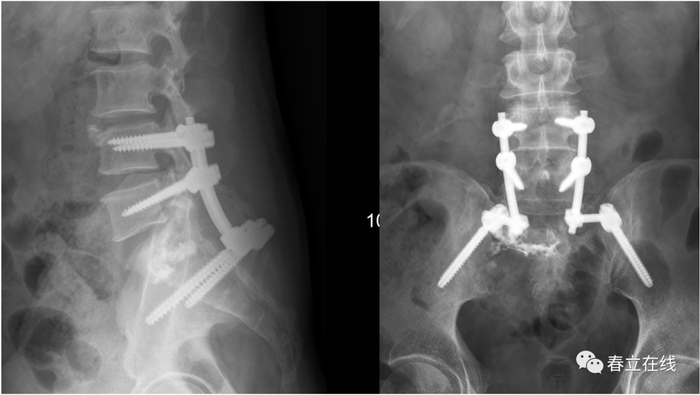

病例1

病例2